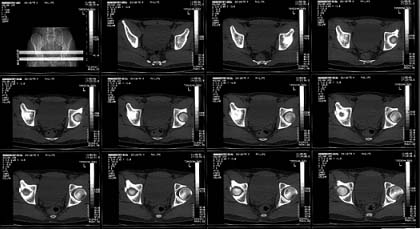

22 yrs man , semiprofessional( he earn some money from playing) basketball player got suffered in car accident.He had hip joint posterior luxation ( Pipkin 4) with little acetabular roof fragments ( nondisplaced) and anterosuperior abruption fracture of the head of the femur.

Additional injuries were severe face wounds. Emergency manipulations were reposition of the hip luxation under the radiologic control and wounds care. After reposition the CT scan was made. We found 2x3cm wide and 0.5 thick OCH fragment outside the joint surfaces , under the caput. The traction was applied.